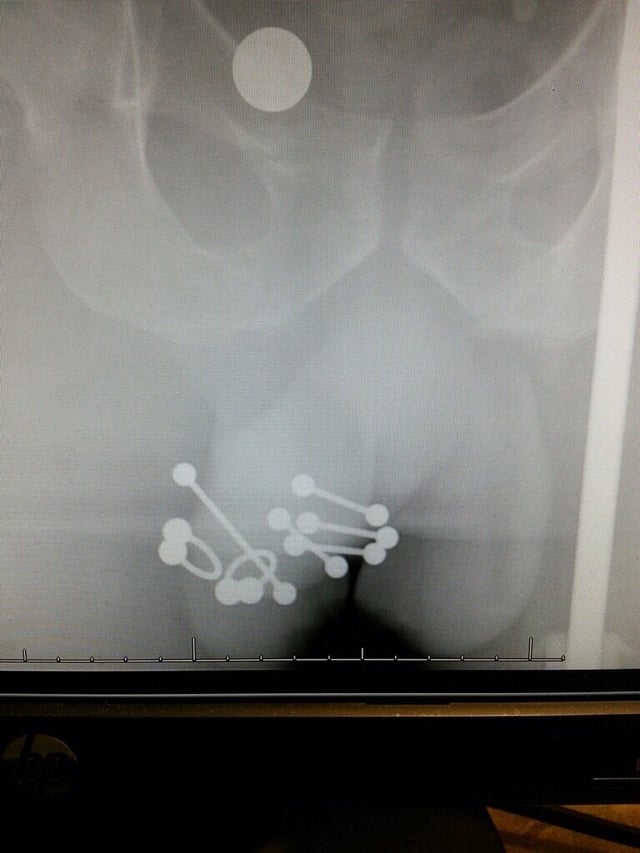

Các Loại Xỏ Khuyên Cậu Nhỏ Phổ Biến Mà Bạn Nên Biết

Thế giới xỏ khuyên vùng kín nam giới rất đa dạng, với nhiều vị trí và kiểu dáng khuyên khác nhau. Mỗi loại đều có những đặc điểm và trải nghiệm riêng biệt. Dưới đây là một số loại phổ biến nhất:

Xỏ khuyên Prince Albert (PA)

Đây là một trong những kiểu xỏ khuyên dương vật phổ biến nhất. Khuyên đi qua niệu đạo và thoát ra ở mặt dưới của quy đầu. Nó thường được cho là giúp tăng khoái cảm khi quan hệ.

Xỏ khuyên Frenum

Khuyên được đặt ở mặt dưới của dương vật, ngay dưới quy đầu, xuyên qua dây hãm. Nhiều người chọn kiểu này để tăng cảm giác tại vùng đó.

Xỏ khuyên Apadravya và Ampallang

- Apadravya: Khuyên xuyên qua quy đầu theo chiều dọc.

- Ampallang: Khuyên xuyên qua quy đầu theo chiều ngang.

Cả hai loại này đều được biết đến là có thể mang lại cảm giác mạnh mẽ cho cả người đeo và bạn tình.

Xỏ khuyên Dydoe

Dạng khuyên này thường được đặt trên vành quy đầu, giúp tăng cường cảm giác tại vùng này.

Xỏ khuyên Scrotum (hoặc Hafada)

Không trực tiếp trên dương vật, mà là ở da bìu. Đây là lựa chọn mang tính thẩm mỹ và cá nhân hóa cao.